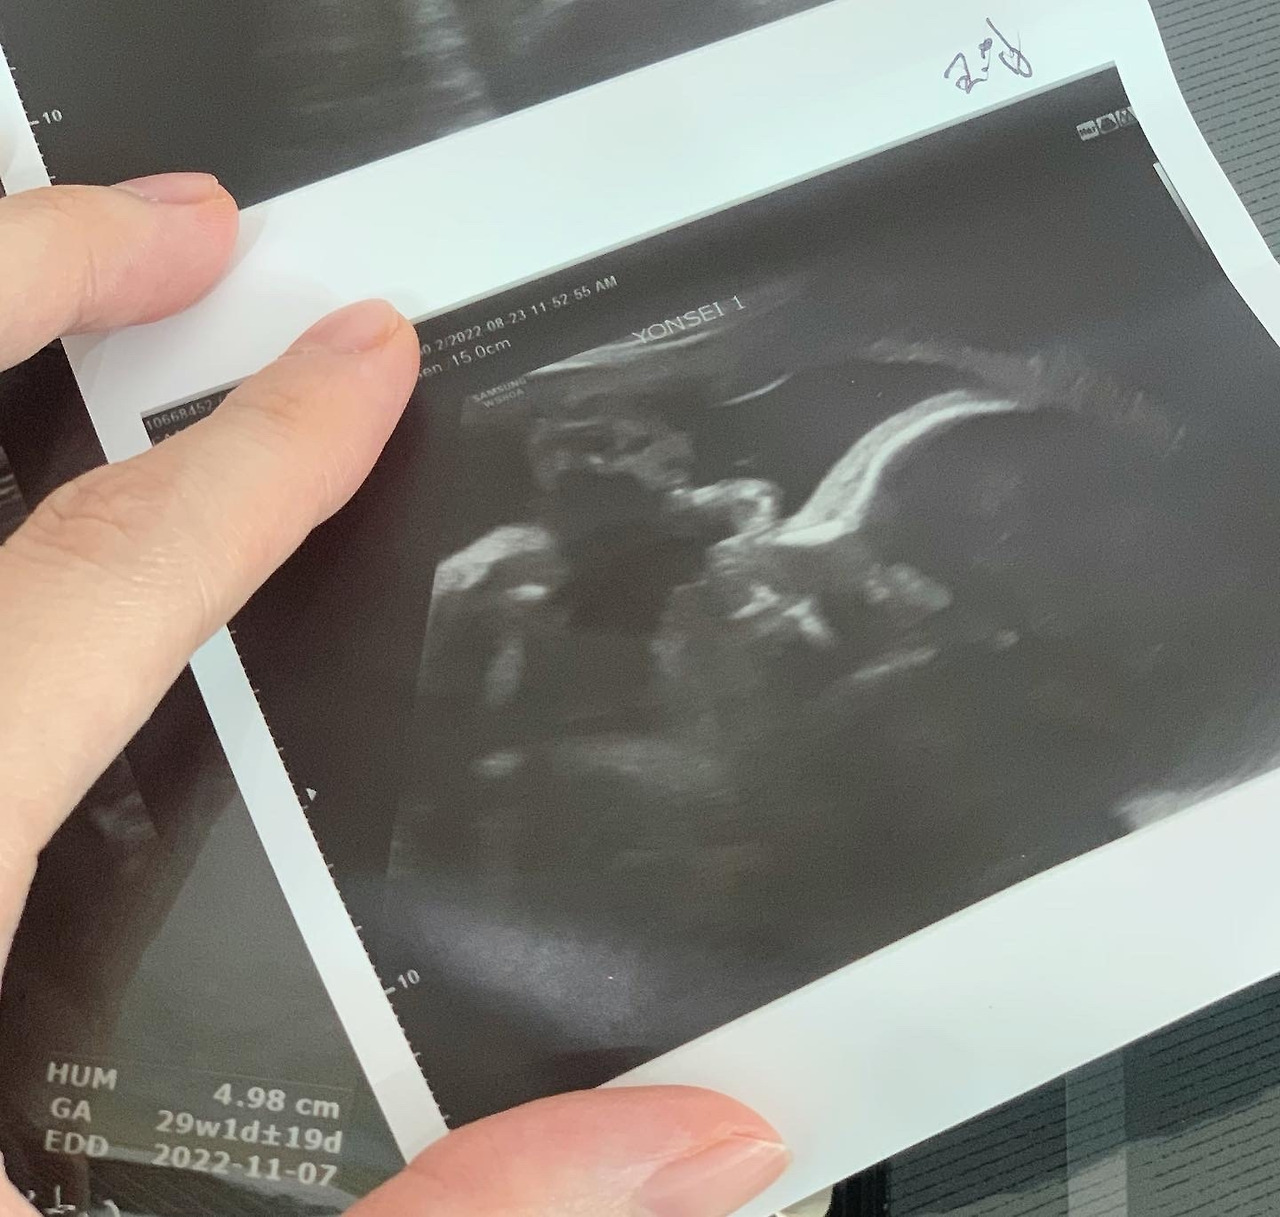

혈압을 재고, 체중과 키를 재고 기다렸다. 이곳은 이전 병원과 다르게 소변 검사는 없었다.(당 검사?) 그리고 초음파를 기다리다가 순서가 되어 들어갔다. 꽤 오랜 시간 초음파를 봐주셨고 사진도 많이 주셔서 조금 놀랐는데 알고 보니 일반 초음파가 아니라 정밀 초음파였고, 내가 남편에게 "대학병원은 사진을 많이 안 준대!"라고 한 말을 듣고 더 많이 뽑으셨다고 말씀해 주셨다.(정말인지는 몰라도 감사했다. 임산부에게 아가 사진은 참 소중 소중)

이전 병원에서 정밀 초음파를 볼 땐 하나하나 설명도 친절하게 해 주셨는데 역시 대학병원은 딱히 그런 건 없었다. 그냥 선생님께서 꽤 오랜 시간을 보셨고 정상이라고만 하셨다. 혹시나 해서 남편에게 영상을 남겨달라고 부탁을 했고 다행히 찍으면 안 되다는 말이 없어서 영상을 간직할 수 있었다. (하지만 남편이 제대로 못 찍음..ㅎㅎ)

나는 이제 대충 어디가 어디구나가 보이는데, 남편은 전혀 어디가 어디인지 구분을 못하더라 ㅎㅎ

근데 또 설명도 안 해주시니 멍 때리고 있던 남편..ㅎㅎ

그나마 잘 나온 다올이 입과 코, 그리고 옆태!

나머지 사진들은 대부분 장기들 사진이라....! 그렇게 초음파를 찍고 사진을 받고 또 대기를 하였다.